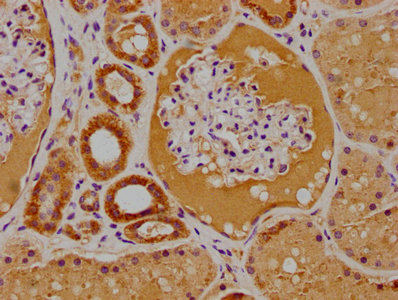

IHC image of CSB-PA018996LA01HU diluted at 1:100 and staining in paraffin-embedded human kidney tissue performed on a Leica BondTM system. After dewaxing and hydration, antigen retrieval was mediated by high pressure in a citrate buffer (pH 6.0). Section was blocked with 10% normal goat serum 30min at RT. Then primary antibody (1% BSA) was incubated at 4°C overnight. The primary is detected by a biotinylated secondary antibody and visualized using an HRP conjugated SP system.